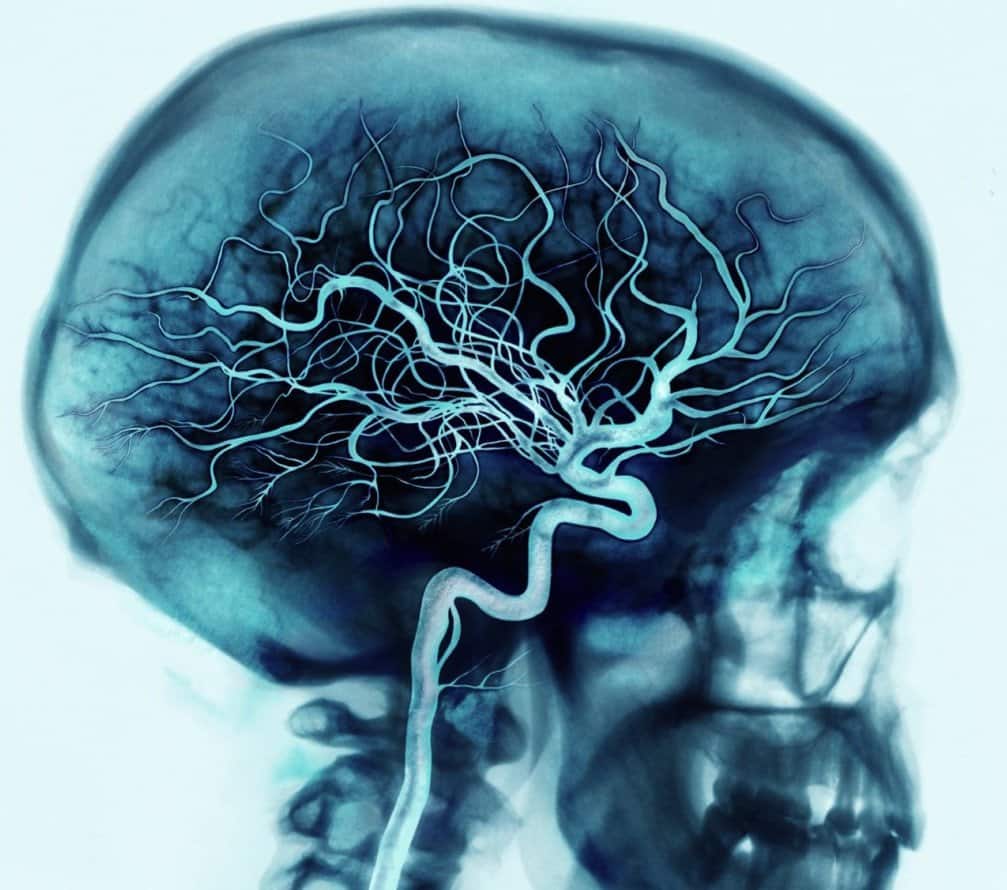

Ангиография – это процедура медицинского обследования, которая использует рентгеновские лучи и контрастное вещество для визуализации кровеносных сосудов в организме. Этот метод является ключевым инструментом в диагностике различных сосудистых заболеваний, таких как атеросклероз, тромбозы, аневризмы и опухоли. В данной статье мы рассмотрим основы ангиография, ее процесс, индикации и роль в современной медицинской практике.

Процедура ангиографии начинается с введения контрастного вещества в кровеносный сосуд путем инъекции через катетер. Это контрастное вещество делает сосуды видимыми на рентгеновских снимках, что позволяет врачам оценить состояние и функцию сосудов. Существует несколько видов ангиографии, включая коронарную ангиографию (для изучения артерий сердца), ангиографию сосудов головного мозга, периферическую ангиографию (для изучения сосудов конечностей) и т.д.